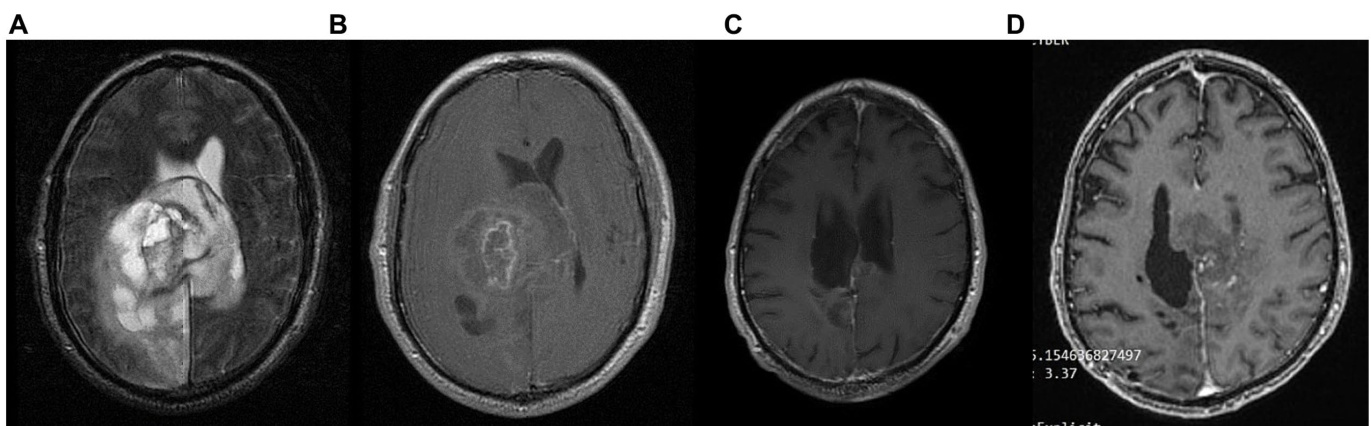

A 41-year-old man was diagnosed with GBM of the left temporal lobe on December 2016 following a brain MRI (Figure 3). The presenting symptom was persistent headache and gradual wordfinding difficulty (anomic aphasia). He underwent surgical resection in January 2017, followed by 30 sessions of radiotherapy $(60\mathrm{Gy})$ along with chemotherapy (temozolomide). His to pathological examination was typical of GBM with IDH1-negative/MGMT-nonmethylated (Figure 4). On March 2017, the patient was started on a calorie restricted 1.4:1 ketogenic diet as adjunctive therapy (Table 3). Blood ketones and glucose levels were self-monitored daily. The patient achieved adequate ketosis during the first week of instituting the ketogenic diet and maintained high ketone levels $\left(3{-}4\mathrm{mmol/L}\right)$ and adequate blood glucose levels $\mathrm{(60-90~mg/dL)}$ ) throughout the observational period. The ketogenic diet was well tolerated, with only mild gastrointestinal side effects (constipation). In addition, he received temozolomide, initially dosed at $100\mathrm{mg/m^{2}/d a y}$ every other week. After 1 month, his dose increased to $200\mathrm{mg/m^{2}/d a y}$ on the same schedule, without toxicities. Temozolomide maintenance treatment lasted for 2 years. Serial MRI brain imaging was obtained every 4 months. His follow-up brain MRI 79 months after diagnosis shows no evidence of tumor recurrence (Figure 3). The patient reports a residual mild anomia and is currently working as a teacher. His most recent ECOG grade is 0.

一名41岁男性患者于2016年12月经脑部MRI (图3) 确诊为左颞叶胶质母细胞瘤 (GBM) 。主要症状为持续性头痛和渐进性命名障碍 (命名性失语) 。2017年1月接受手术切除,随后进行30次放疗 $(60\mathrm{Gy})$ 联合替莫唑胺化疗。病理检查显示典型IDH1阴性/MGMT非甲基化的GBM特征 (图4) 。2017年3月起,患者开始采用1.4:1热量限制生酮饮食作为辅助治疗 (表3) ,每日自行监测血酮和血糖水平。实施生酮饮食首周即达到理想酮症状态,并在整个观察期间维持较高酮体水平 $\left(3{-}4\mathrm{mmol/L}\right)$ 和正常血糖范围 $\mathrm{(60-90~mg/dL)}$ 。该饮食方案耐受性良好,仅出现轻微胃肠道副作用 (便秘) 。同步接受替莫唑胺治疗,初始剂量为隔周 $100\mathrm{mg/m^{2}/d a y}$ ,1个月后按相同方案增至 $200\mathrm{mg/m^{2}/d a y}$ ,未出现毒性反应。替莫唑胺维持治疗持续2年,每4个月进行系列脑部MRI复查。确诊79个月后的随访MRI显示无肿瘤复发迹象 (图3) 。患者目前遗留轻度命名障碍,从事教师职业,最新ECOG评分为0级。

FIGURE 3 Patient 1: (A) Pre-operative brain MRI (T2/FLAIR) (B) Pre-operative brain MRI (T1 with contrast) (C) 38-month follow-up brain MRI (T1 with contrast) (D) 80-month follow-up brain MRI (T1 with contrast).

图 3: 患者1: (A) 术前脑部MRI (T2/FLAIR) (B) 术前脑部MRI (T1增强) (C) 38个月随访脑部MRI (T1增强) (D) 80个月随访脑部MRI (T1增强)。